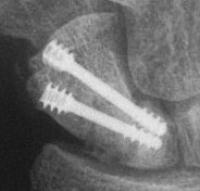

Case 8. Transscaphoid perilunate fracture dislocation...

Two screws put in dorsally, LT ligament reinforced with a strip of extensor retinaculum left attached to the triquetrium and anchored into the lunate; temporary capitolunate pin.

Click for larger image